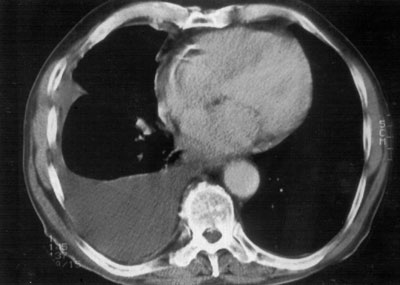

Radiological evaluation is essential to determine if a patient with MPM has potentially resectable disease. Posteroanterior and lateral chest roentgenogram (Figure 1), computerized tomography (CT scan) of the chest and upper abdomen (Figure 2), and magnetic resonance imaging (MRI) of chest have been the most widely used modalities. CT scan provides an estimate of tumor burden and extent of tumor both locally and distantly. MRI can supplement the CT scan for detection of tumor extension into the mediastinum or the abdomen. More recently, positron emission tomography (Figure 3) has been used to determine if a patient has early resectable disease based on no evidence of contralateral disease or distant metastasis. Early results are promising [6].